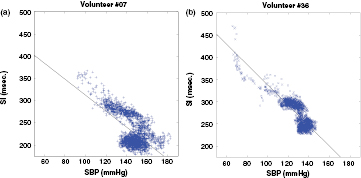

The level of agreement between the surrogates presents the best results (i.e. SI) and the SBP are illustrated by the regression plots present in figures 12(a) and (b), for two volunteers. A linear model SBP = A * SI + B was applied on the data extracted from volunteer 7 (figure 12(a)) and volunteer 36 (figure 12(b)). For volunteer 7, the best linear fit corresponds to a negative slope A = −1.8, which is very far from the unit. For volunteer 36, the best linear fit corresponds to similar slope A = −2.28. From figure 12 it is possible to observe a strong linear and negative correlation between SI and SBP, especially for lower values of SBP (high values of SI). The higher dispersion SI/SBP points for high SBPs, particularly above 130 mmHg, suggest a higher uncertainty in the SI measurement, resulting from the increasingly overlapping of the forward and reflected waves.

Figure 12. Regression plots of SI-SBP. (a) Volunteer #07 (ρ = 0.0.64): best linear fit SBPe = −1.8* SI + 491. (b) Volunteer #36 (ρ = −0.84): best linear fit SBPe = −2.28* SI + 565.6.